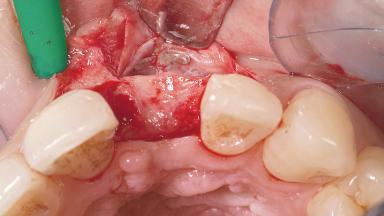

Late Placement of an Implant in a Maxillary Left Central Incisor Site

A 30-year-old female patient had lost tooth 21 and was referred to our clinic for consultation and treatment. Due to advanced apical infection, tooth 21 had been extracted two months earlier at another clinic and an acrylic-resin tooth had been bonded to the adjacent teeth. The patient desired implant treatment to avoid any damage to the adjacent natural teeth. While the patient had no history of any systemic disorder, she was a heavy smoker and exhibited medium to advanced periodontitis in the entire jaw. After the initial treatment to achieve a pocket probing depth of less than 4 mm and no bleeding on probing, a decrease in the height of the papillae mesial and distal to the extraction site and overall gingival recession were observed.

Bone Augmentation Horizontal|Staged

Augmentation Materials Autogenous chips|Membrane

Soft Tissue Grafting Simultaneous